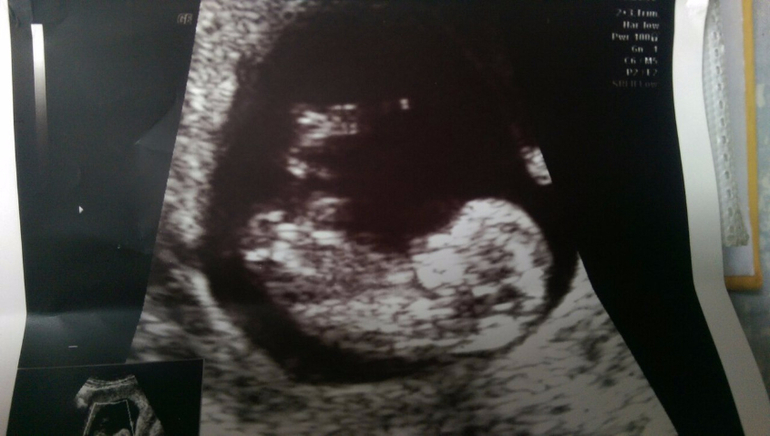

Дальше живот тянет, сны стрёмные....То на УЗИ не хорошие результаты и вся этакая туфталогия. Я хоть и не первородка, но на столько я желала второго ребёнка,беременность, что я очень переживала..... На узи ведь по факту плановое уже нужно было через неделю....Но я труханула и полетела сегодня. Срок 10+5.

Итак,узи показало мне моего прекрасного малышааааа!!!!Который растёёёёёт,у которого бьётся быстренько сердечкоооо!!!!!! Мой сладкий....Ручки,ножки всё уже ееееесть!!!!

Ну скажите,кому бы не радостно было,а?)))Уже на человечка похож более менее!!!!!!!!!!

Ктр 41мм и развиты мы на 11 недель. Урааа!!!!! Старше своего срока...Я рада что мой малыш прекрасно себя чувствует у меня в матке!!!!У меня внутри!!!!

Ну и фото....